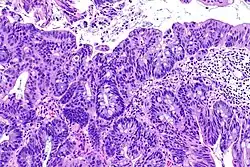

Rak urotelialny pęcherza moczowego

Inwazyjny (naciekający) rak urotelialny jest definiowany jako obecność inwazji nowotworowej poniżej błony podstawnej urotelium[74]. Makroskopowo inwazyjne nowotwory urotelialne mogą przyjmować formę brodawkowatą, polipowatą, guzkową, litą, tworzyć rozlany naciek ściany pęcherza moczowego. Zmiany mogą występować pojedynczo lub wieloogniskowo[75]. Typowo większość guzów pT1 jest brodawczakowata o niskim lub wysokim stopniu złośliwości histologicznej, z kolei guzy o większym zaawansowaniu pT2–T4 wykazują morfologię niebrodawczakowatą i cechują się wysokim stopniem złośliwości[76][77].

Mikroskopowo w utkaniu obecne są komórki tworzące gniazda, sznury komórek lub pojedyncze komórki pooddzielane desmoplastycznym podścieliskiem[76][78]. Możliwy jest bardziej rozlany wzór wzrostu nowotworu, w którym komórki tworzą arkusze, przy czym również w takim utkaniu spotyka się ogniskowo występujące gniazda komórek[78]. Komórki cechują się umiarkowaną do obfitej ilością amfofilnej lub eozynofilnej cytoplazmy i dużym hiperchromatycznym jądrem komórkowym. Jądra komórkowe wykazują znaczną pleomorficzność, nieregularne, kanciaste granice. Liczba i wygląd jąderek wykazuje znaczną zmienność. Gniazda komórek nowotworowych zwykle indukują reakcję desmoplastyczną podścieliska. Obecne są liczne figury mitotyczne i możliwa jest obecność nieprawidłowych figur mitotycznych. W podścielisku większości guzów jest obecny naciek limfocytów i komórek plazmatycznych, naciek najczęściej jest wyrażony ogniskowo od łagodnego do umiarkowanego stopnia, ale może być nasilony i rozlany[76][78]. Może być widoczna inwazja naczyń[78].